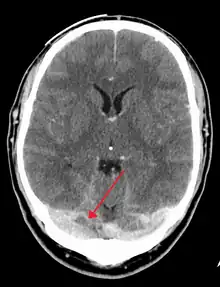

There are various neuroimaging investigations that may detect cerebral sinus thrombosis. Cerebral edema and venous infarction may be apparent on any modality, but for the detection of the thrombus itself, the most commonly used tests are computed tomography (CT) and magnetic resonance imaging (MRI), both using various types of radiocontrast to perform a venogram and visualise the veins around the brain.[4]

Computed tomography, with radiocontrast in the venous phase (CT venography or CTV), has a detection rate that in some regards exceeds that of MRI. The test involves injection into a vein (usually in the arm) of a radioopaque substance, and time is allowed for the bloodstream to carry it to the cerebral veins - at which point the scan is performed. It has a sensitivity of 75-100% (it detects 75-100% of all clots present), and a specificity of 81-100% (it would be incorrectly positive in 0-19%). In the first two weeks, the "empty delta sign" may be observed (in later stages, this sign may disappear).[11]